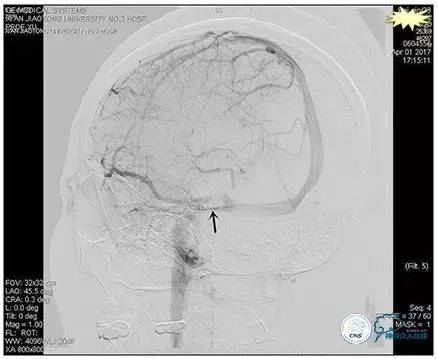

术后造影

术毕远近端压力差为:0